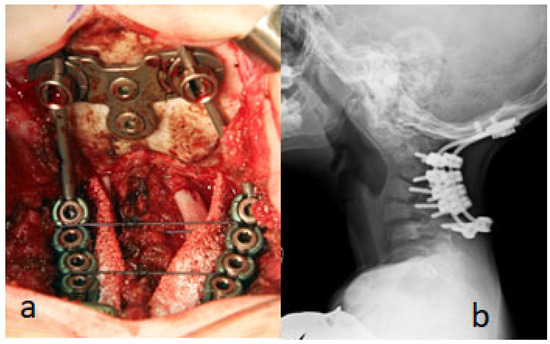

According to the photo (intraoperative), at the end of the surgery 10, 3, and 5 mm screws were inserted in the lateral masses of C3-6 and intralaminar in C7 as well as two standard screws were applied to the occipital plate (Figure 9a). The surgery was followed by breath problems due to chest softness. Therefore, we were obliged to stop the operation every 30 min in order to give the child better oxygenation through lifting the child in our hands. Good neurological recovery was noticeable 2 weeks after surgery. A lateral cervical spine radiograph, ten years after surgery, showed good bone fusion, and the hardware is still stable (Figure 9b). He manifested remarkable improvement.

Figure 9.

(a,b). As shown in the photo (intraoperative), at the end of the surgery 10, 3, and 5 mm screws were inserted in the lateral masses of C3-6 and intralaminar in C7 as well as two standard screws that were applied to the occipital plate (Figure 7a). A lateral cervical spine radiograph, ten years after surgery, showed good bone fusion, and the hardware is still stable (b). Follow up after10 years (2014–2024) showed no neurological deficits. The foot surgery (talipes equinovarus) was made in another hospital. The implants are stable and have good glance, so we decided not to do anterior decompression and fixation.